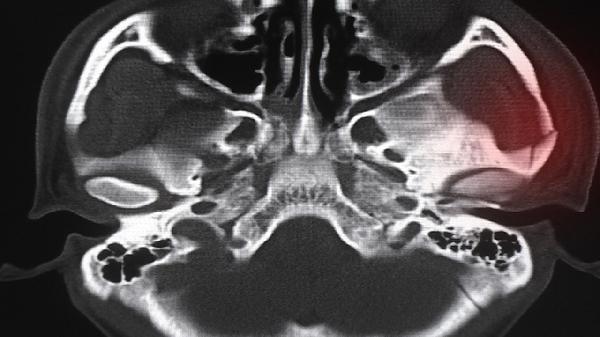

5、抗菌药物:黄脓痰伴白细胞升高提示细菌感染,需经医生评估后使用阿莫西林或头孢呋辛。滥用抗生素会导致耐药性,用药需完成规定疗程。细菌性鼻窦炎通常需要10-14天治疗周期。